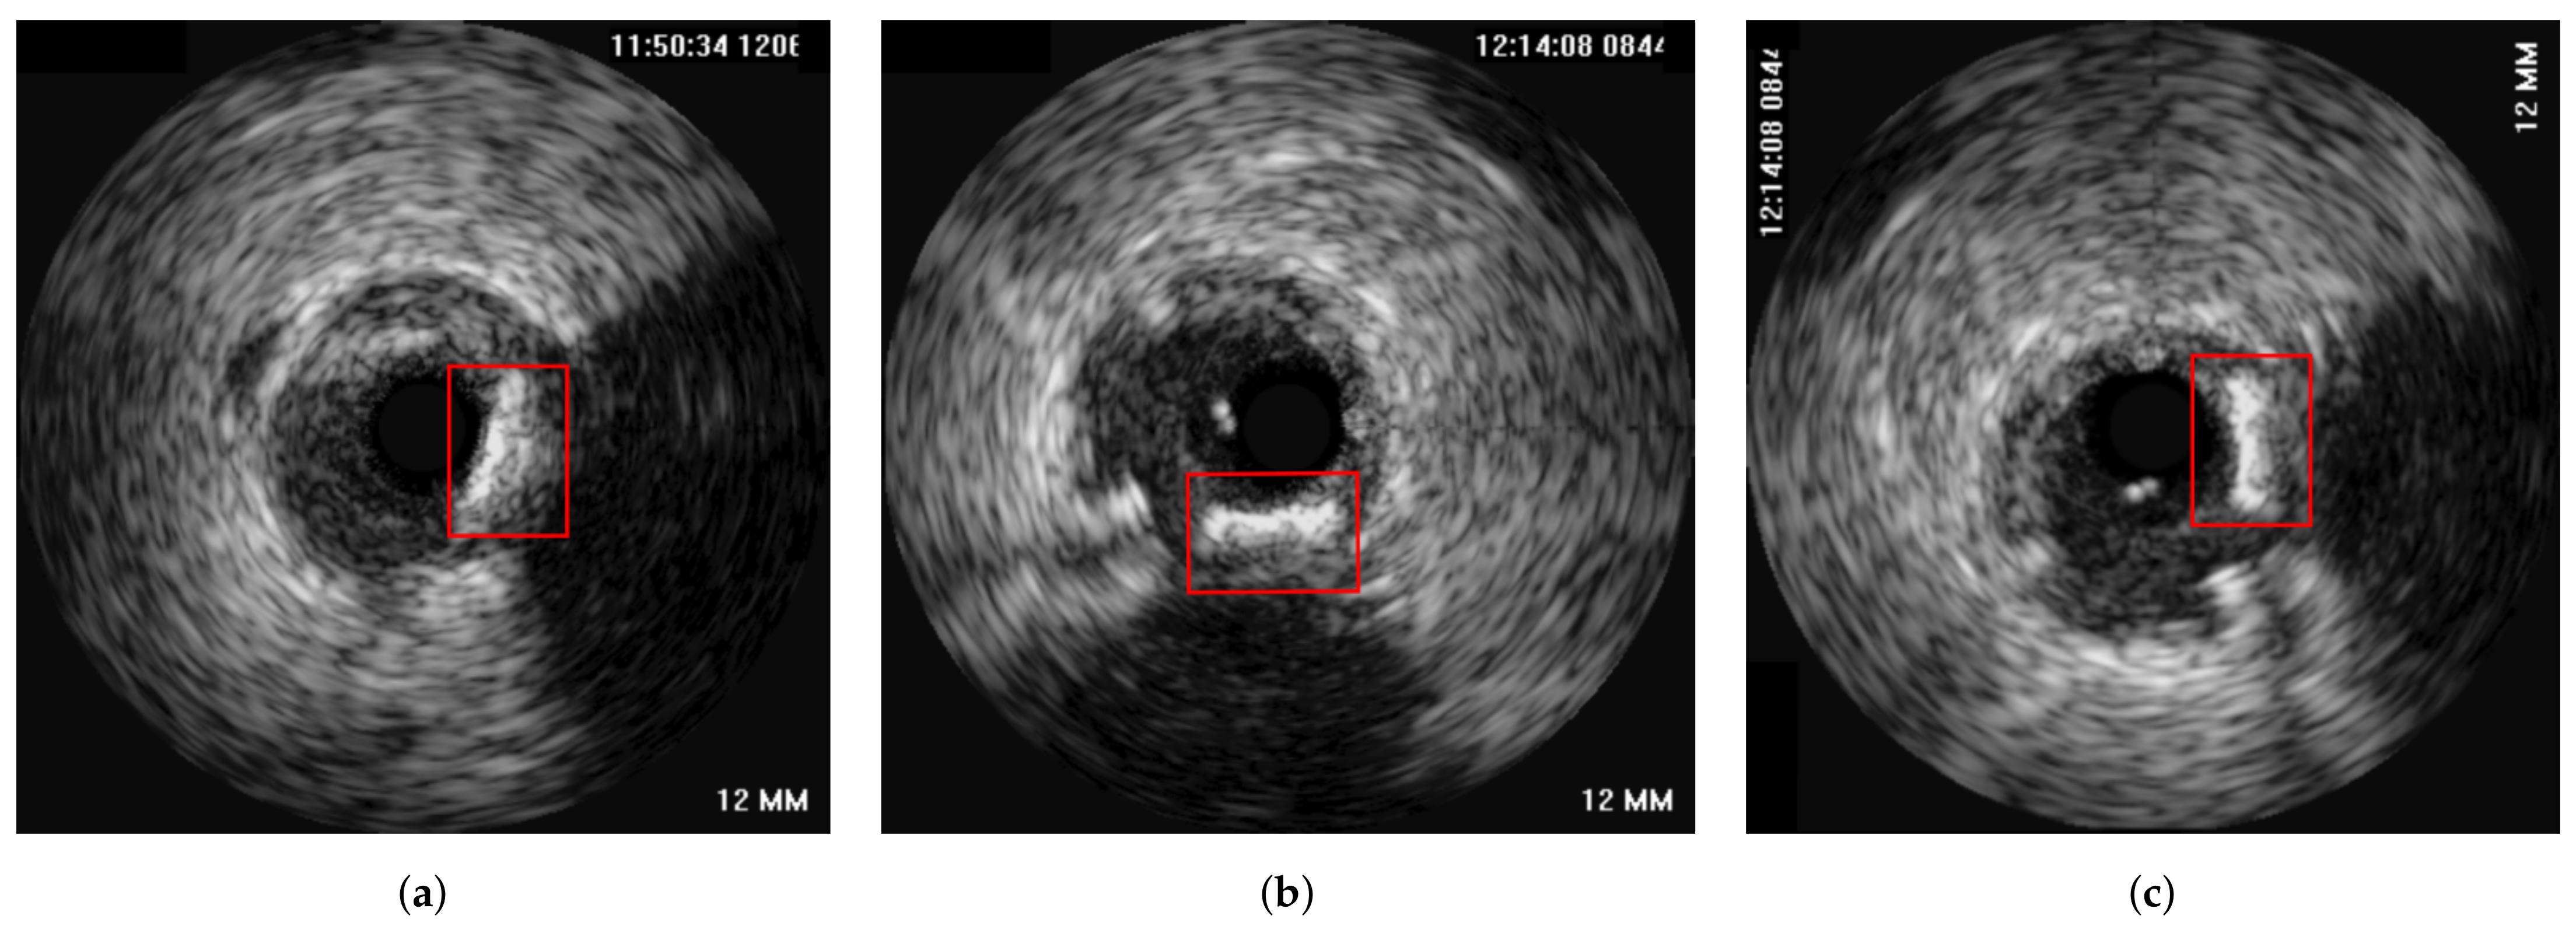

The method was tested on IVUS data from 21 patients from two clinical centres, i.e., University Hospital of Ioannina, Greece and Erasmus EMC, Netherlands. The data of 10 patients consisted of two IVUS pullbacks, corresponding to a pre- and a post-stent deployment (immediately after the procedure) pullbacks respectively. For the remaining 11 patients, the first pullback was from a pre-stent deployment examination and the second one from a follow-up IVUS examination (after a few months). As a result the dataset used was heterogeneous which was a prerequisite for testing the robustness of the proposed method. The mean pullback length was 118 frames. In this study, two different experiments were conducted. The first experiment regarded the evaluation of the method on synthetic data, for which the ground truth information for each registration stage was available. The second experiment was based on the in-vivo data, for which ground-truth frame correspondence was available for the longitudinal registration based on the presence of specific landmarks (i.e., bifurcations and calcifications), which were easy to be detected across IVUS examinations. These landmarks were annotated by an expert cardiologist based on careful examination of each pullback pair. In addition, the location of each landmark was marked using a manual annotation tool by the expert cardiologist to be used as ground truth when evaluating the axial registration. Figure 4 presents an example of corresponding frames with two annodated landmarks (a bifurcation and a calcification).

Figure 4. Two corresponding pairs of annotated frames based on the presence of a bifurcation (a,b) and calcification (c,d), which are highlighted with a red box in the images.